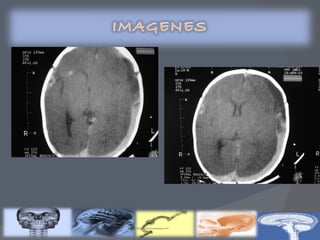

Clasificación de Volpe por ultrasonido transfontanelar Clasificación de Papile por tomografía axial computarizada Gravedad de la HIV Descripción GRADO I Hemorragia de la matriz germinal mínima(<10% del área ventricular) GRADO  II Hemorragia del área ventricular de 10 a 50% GRADO  III Hemorragia del área ventricular >50% Hemorragia intracerebral u otra lesión parenquimatosa Gravedad de la HIV Descripción % de HIV GRADO  I Hemorragia de la matriz germinal 40 GRADO II Hemorragia con tamaño normal de los ventrículos 30 GRADO III Hemorragia  con dilatación ventricular 20 GRADO IV Hemorragia ventricular, más parenquimatosa 10

GRADO 1 La hemorragia está localizada únicamente en la matriz germinal subependimaria GRADO 2 Contenido de sangre intraventricular que ocupa menos del 50% del área ventricular en una proyección parasagital GRADO 3 La sangre ocupa un área mayor del 50%, distendiendo el ventrículo Cuando existe una hemorragia intraventricular masiva que sobredistiende de forma muy importante los ventrículos laterales y, en general, todo el sistema ventricular está ocupado:tercer y cuarto ventrículos y espacio subaracnoideo de fosa posterior (cisterna magna)

Clasificación de Volpepor ultrasonido transfontanelar Clasificación de Papile por tomografía axial computarizada Gravedad de la HIV Descripción GRADO I Hemorragia de la matriz germinal mínima(<10% del área ventricular) GRADO II Hemorragia del área ventricular de 10 a 50% GRADO III Hemorragia del área ventricular >50% Hemorragia intracerebral u otra lesión parenquimatosa Gravedad de la HIV Descripción % de HIV GRADO I Hemorragia de la matriz germinal 40 GRADO II Hemorragia con tamaño normal de los ventrículos 30 GRADO III Hemorragia con dilatación ventricular 20 GRADO IV Hemorragia ventricular, más parenquimatosa 10

GRADO 1 Lahemorragia está localizada únicamente en la matriz germinal subependimaria GRADO 2 Contenido de sangre intraventricular que ocupa menos del 50% del área ventricular en una proyección parasagital GRADO 3 La sangre ocupa un área mayor del 50%, distendiendo el ventrículo Cuando existe una hemorragia intraventricular masiva que sobredistiende de forma muy importante los ventrículos laterales y, en general, todo el sistema ventricular está ocupado:tercer y cuarto ventrículos y espacio subaracnoideo de fosa posterior (cisterna magna)